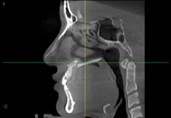

Полная проверка состояния носа благодаря снимкам КТ.

Благодаря 3Д-КТ снимкам возможно рассмотреть в мельчайших подробностях не только состояние костей носа, но и форму, состояние и размеры мягких тканей вокруг него, что позволяет правильно составить безопасный план операции.

При необходимости использования во время операции хрящевой перегородки носа, очень важен подробный анализ размера и формы хрящевой перегородки. Такой анализ позволяет составить план операции в мельчайших подробностях.